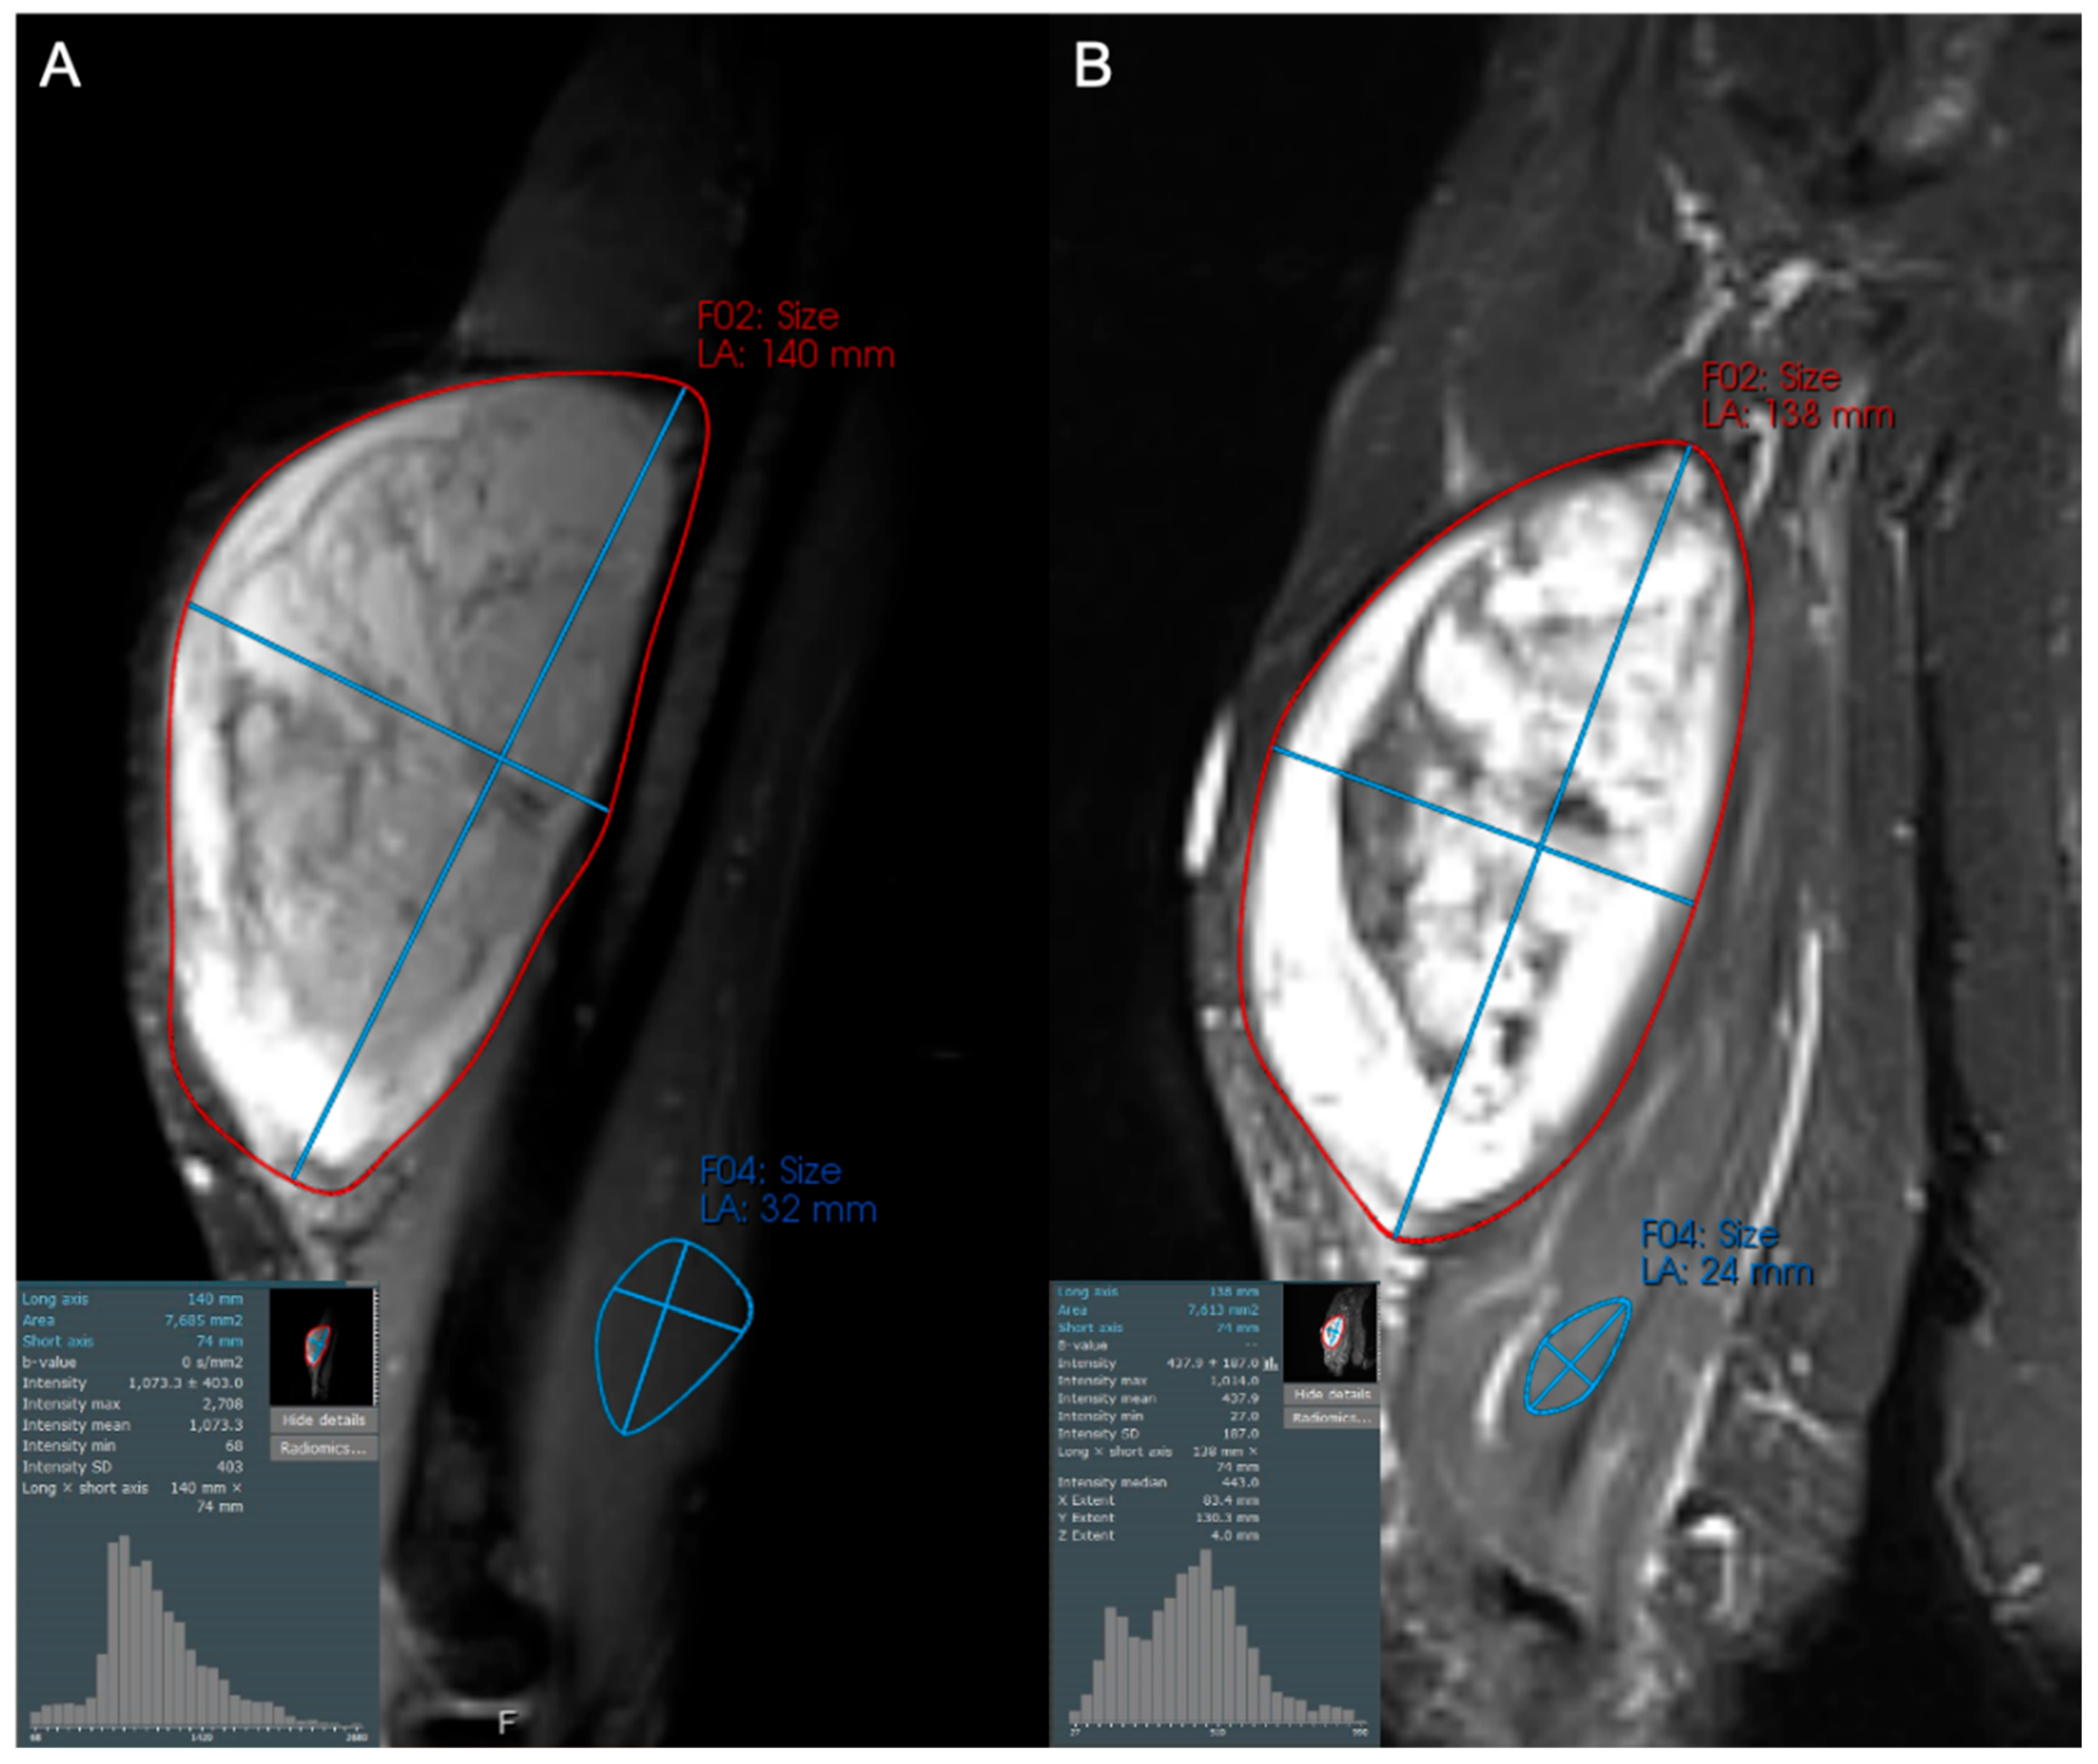

- Subhawong, T.K.; Feister, K.; Sweet, K.; Alperin, N.; Kwon, D.; Rosenberg, A.; Trent, J.; Wilky, B.A. MRI Volumetrics and Image Texture Analysis in Assessing Systemic Treatment Response in Extra-Abdominal Desmoid Fibromatosis. Radiol. Imaging Cancer 2021, 3, e210016. [Google Scholar] [CrossRef]